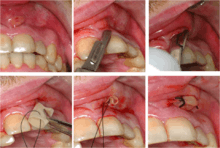

Gutta-percha point indicating abscess origin

Dental abscesses

A general principle concerning dental abscesses is ubi pus, ibi evacua ("where there is pus, drain it"), which applies to any case where there is a collection of pus in the tissues (such as a periodontal abscess, pericoronal abscess, or apical abscess). The pus within the abscess is under pressure, and the surrounding tissues are deformed and stretched to accommodate the swelling. This leads to a sensation of throbbing (often in time with the pulse) and constant pain. Pus may be evacuated via the tooth by drilling into the pulp chamber (an endodontic access cavity). Such a treatment is sometimes termed open drainage. Drainage can also be performed via the tooth socket, once the causative tooth is extracted. If neither of those measures succeeds, or they are impossible, incision and drainage may be required, in which a small incision is made in the soft tissues directly over the abscess at the most dependent point. A surgical instrument such as a pair of tweezers is gently inserted into the incision and opened, while the abscess is massaged to encourage the pus to drain out. Usually, the reduction in pain when the pus drains is immediate and marked as the built up pressure is relieved. If the pus drains into the mouth, there is usually a bad or offensive taste.